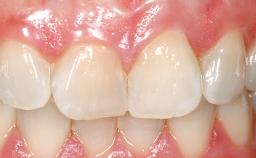

A 33-year-old female patient presented with an upper left central incisor that required extraction after a failed endodontic therapy. The tooth had been traumatized when the patient was a teenager and had undergone several endodontic treatments, including two apicectomy procedures. The patient was in good health and did not smoke. Clinical examination showed that the patient had a high lip line. In full smile, the gingival margins of the upper teeth were visible to the first molars. The gingival margins of central incisors 11 and 21 were only just showing. Examination of tooth 21 confirmed that the tooth was mobile and had hypererupted by 1 mm.

Lip Line No exposure of papillae Exposure of papillae Full exposure of mucosa margin

Periodontal Phenotype Low-scalloped, thick Medium-scalloped, medium-thick High-scalloped, thin

Shape of Tooth Crowns Rectangular Triangular

Mesio-Distal Space Symmetry +/- 1 mm of contra-lateral tooth